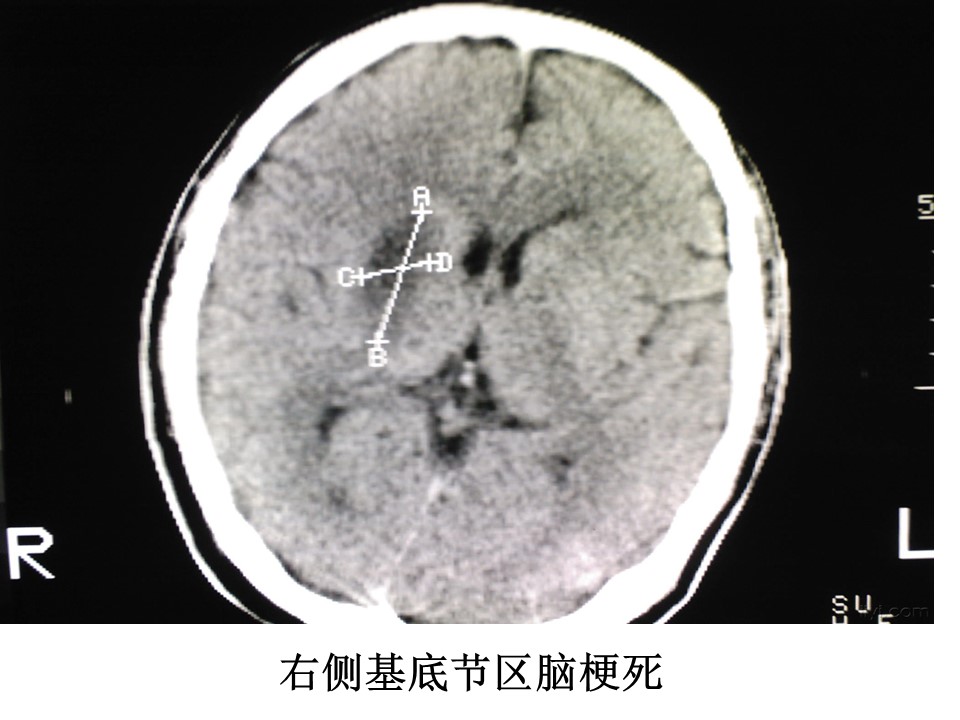

“头颅CT解剖及诊断PPT” 的相关文章